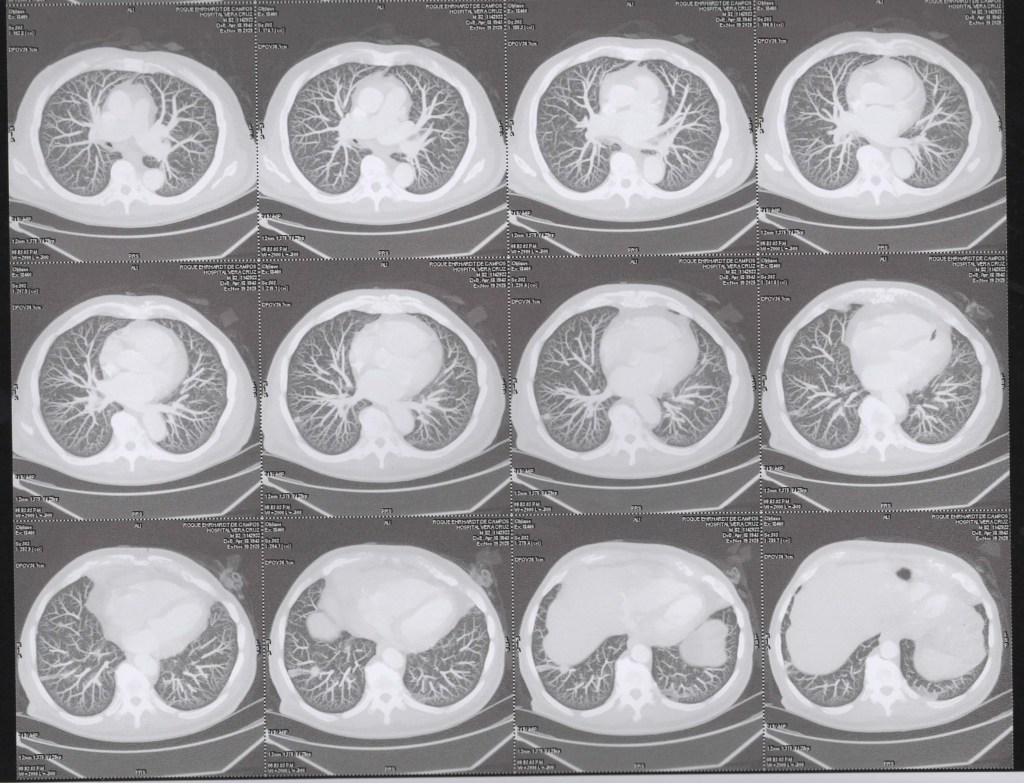

(TC) de Tórax com cortes coronais (vista frontal), em janela pulmonar, com técnica MIP (Maximum Intensity Projection).